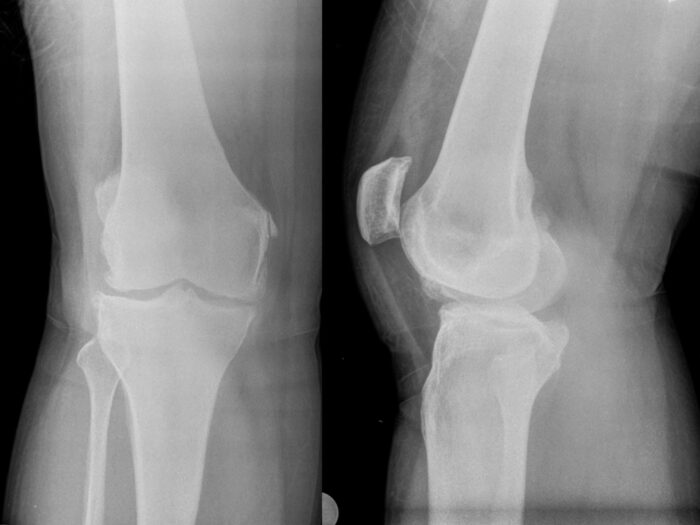

Η οστεοαρθρίτιδα της άρθρωσης του γόνατος αποτελεί τη συχνότερα εμφανιζόμενη μορφή της, ακολουθούμενη από την οστεοαρθρίτιδα των μικρών αρθρώσεων των δακτύλων του χεριού και της άρθρωσης του ισχίου. Στον γενικό πληθυσμό άνω των 40 ετών, το ποσοστό των πασχόντων από το σημαντικό ορθοπαιδικό πρόβλημα της οστεοαρθρίτιδας του γόνατος πλησιάζει το 23%. Ο ακτινολογικός έλεγχος επιβεβαιώνει την αρχική κλινική διάγνωση. Αξίζει ωστόσο να σημειωθεί ότι η ακτινολογική εικόνα δε συμβαδίζει πάντα με την κλινική εικόνα, δηλαδή μπορεί να υπάρχουν έντονα συμπτώματα σε έναν ασθενή με σχεδόν φυσιολογική ακτινογραφία και σχεδόν καθόλου συμπτώματα σε ασθενή με ακτινογραφία προχωρημένης αρθρίτιδας.

Ως τελική θεραπεία ενός ασθενούς που δεν δύναται να ανακουφιστεί με τα προαναφερθέντα συντηρητικά μέτρα, προτείνεται η χειρουργική θεραπεία με τη μέθοδο της αρθροπλαστικής. Πρόκειται για σημαντικό χειρουργείο, που ουσιαστικά αντικαθιστά τις φθαρμένες επιφάνειες των οστών της κνήμης, του μηρού και της επιγονατίδας με μεταλλικές προθέσεις και ένθετα πλαστικού πολυαιθυλενίου. Η επιτυχής έκβαση εξαρτάται από διάφορους παράγοντες, ένας εκ των οποίων είναι και η εξοικείωση και η εκπαίδευση του χειρουργού πάνω στην ορθή χειρουργική τεχνική. Τα τελευταία χρόνια, ολοένα και συχνότερα επιλέγουμε να εκπαιδευτούμε ως χειρουργοί σε μεθόδους ελάχιστης επεμβατικότητας και μικρότερου χειρουργικού τραύματος, προς όφελος της ταχύτερης ανάρρωσης του ασθενούς. Ο σημαντικότερος παράγοντας όμως για την επιτυχή έκβαση του χειρουργείου και την ικανοποίηση του ασθενούς, είναι η πρόταση της χειρουργικής θεραπείας επί σωστών κλινικών και ακτινολογικών ενδείξεων. Ένα τέτοιο παράδειγμα είναι ένας δραστήριος ασθενής με καθημερινό έντονο πόνο, που δεν μπορεί να ανταπεξέλθει στις καθημερινές του δραστηριότητες παρά την εφαρμοζόμενη συντηρητική θεραπεία, για διάστημα άνω των 6 μηνών. Φυσικά, εξυπακούεται πως η προτεινόμενη θεραπεία για κάθε ασθενή εξατομικεύεται από τον ιατρό του.